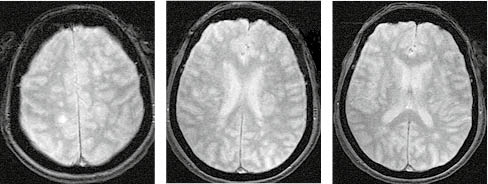

За МРТ-зображення головного мозку пацієнта з ГРЕМ у режимі Т2/Flair та Т1 із внутрішньовенним контрастуванням візуалізуються двобічні вогнища, гіперінтенсивні за Т2/Flair, які в переважно накопичують контраст і розташовані на рівні базальних ядер і таламусів, що є типовою клінічною ознакою ГРЕМ (рис. 2).

/images/nn257-1622023r2_.jpg)

У режимі Т2*/T2 GRE на МРТ-зображенні головного мозку пацієнта з ГРЕМ візуалізуються двобічні гіперінтенсивні вогнища без геморагічного компоненту, що є типовою ознакою ГРЕМ, на відміну від гострого геморагічного лейкоенцефаліту (хвороби Херста) (рис. 3).

/images/nn257-1622023r3_.jpg)